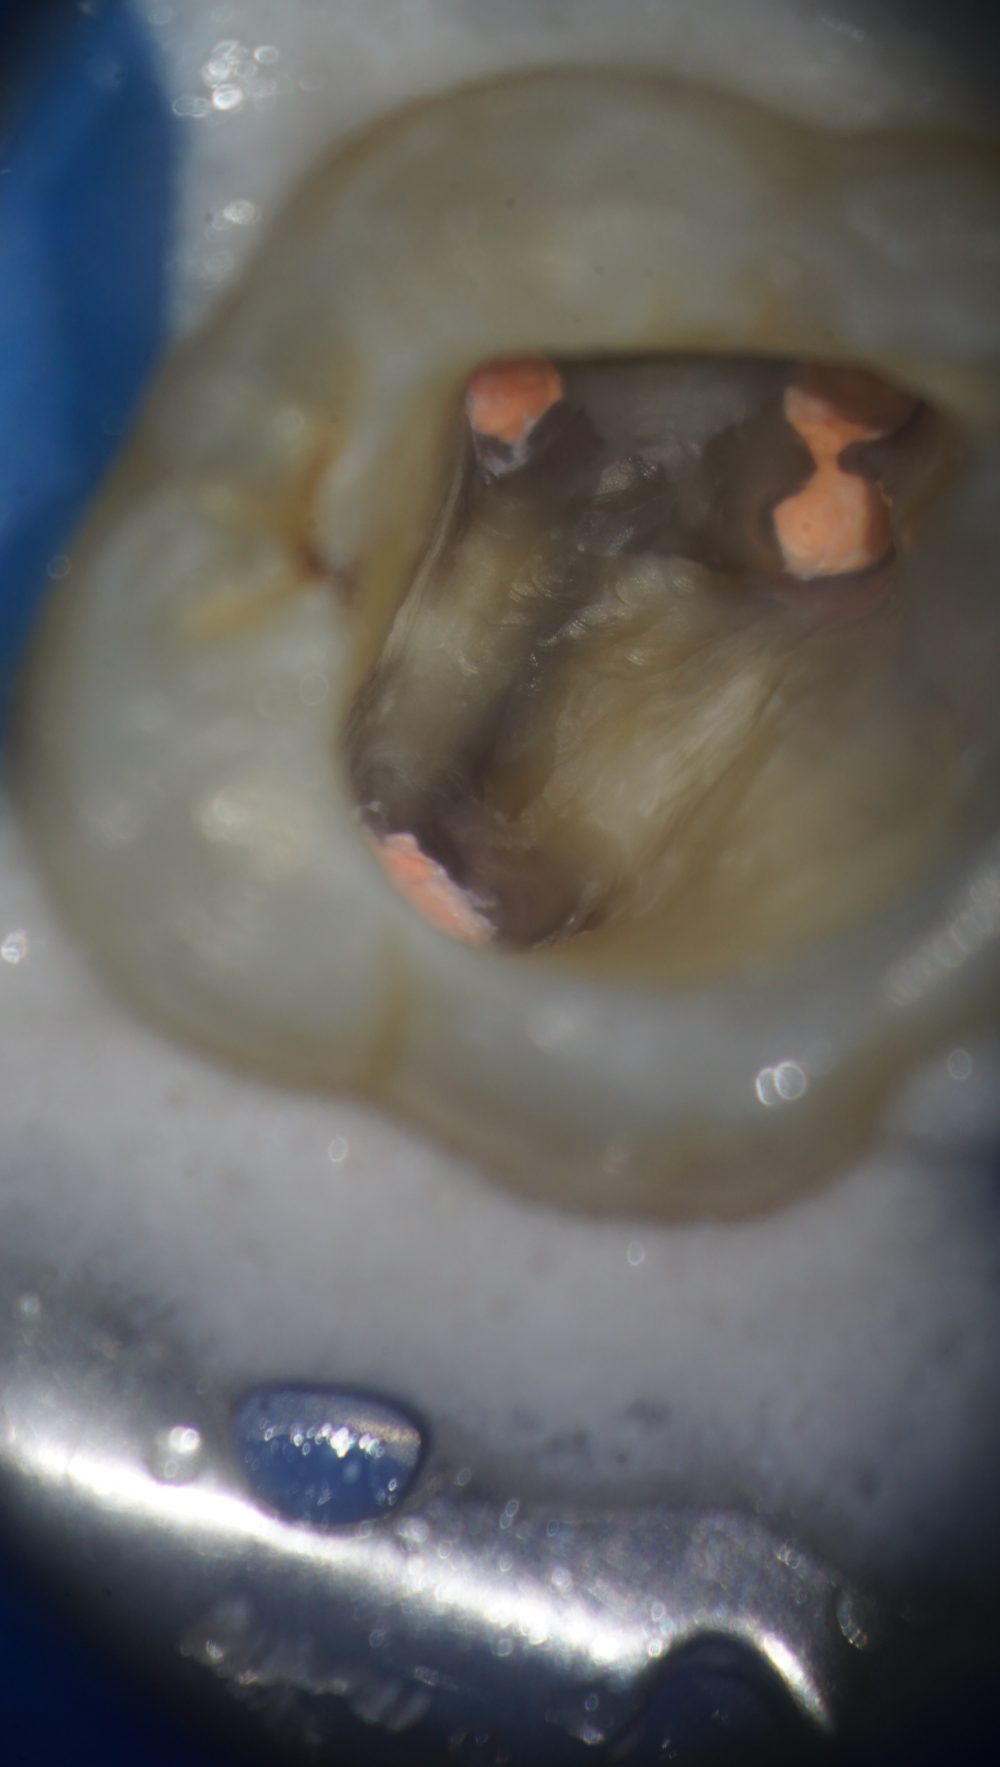

マイクロで見ると、こんな感じで怪しい影が見えるわけですね。

写真はすでにちょびっと拡大しています。

きれいに拡大するとこんな感じ。

MB1とMB2がイスムスのようになっていますね。